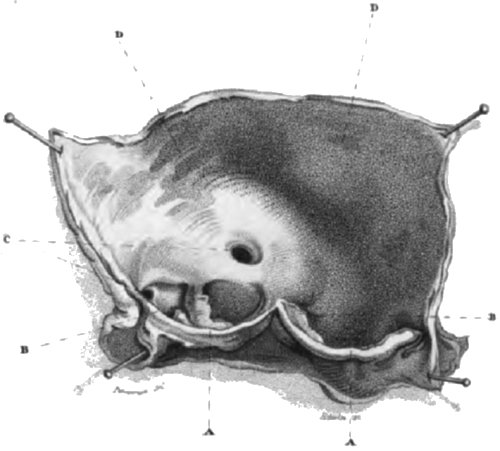

PLATE I.

Appearance of the valves of the aorta in Case 3d, Article 10.